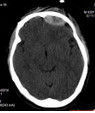

可行常規物理檢查。2.CT檢查在頭部外傷時CT是最重要的影像學診斷方法,對新鮮出血敏感性高,並能顯示水腫及顱內壓增高繼發腦疝等重要病變。